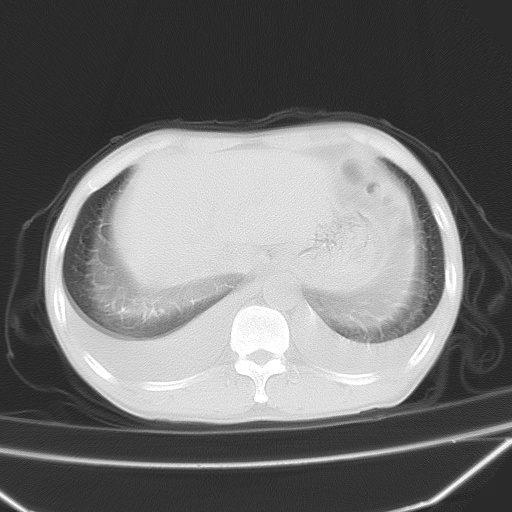

男、42岁、咯血3天。既往有甲亢、贫血、血尿蛋白尿史多年。血象:wbc:6.   中性粒:70.6%。

双肺堆成磨玻璃影,双测胸腔积液。考虑:肺水肿、间质性肺炎、真菌感染、ards、hiv感染、肺出血。

双肺野广泛对称性磨玻璃影、实变影,以肺门为中心,主要分布于内中带,符合典型肺泡性肺水肿;伴双侧胸腔少量游离积液。结合患者既往病史且咯血就诊,支持多因素(尿毒症等)所致之肺水肿、肺出血、胸水;影像表现暂不考虑心源性水肿,且症状也不太符。需密切随诊结合临床治疗等进一步明确。